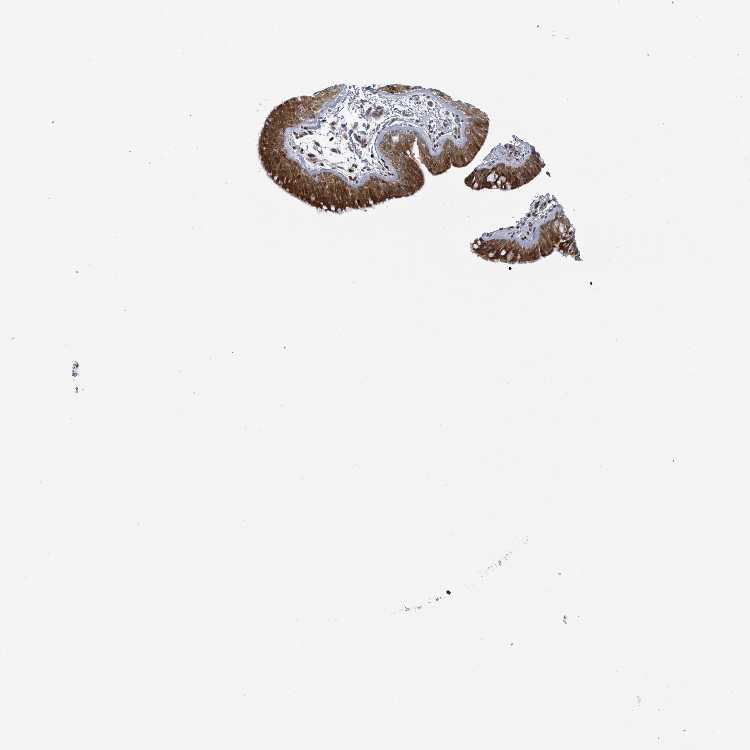

SOFT TISSUE 1 - Antibody stainingi

Antibody staining in the annotated cell types in the current human tissue is reported as not detected, low, medium, or high, based on conventional immunohistochemistry profiling in selected tissues. This score is based on the combination of the staining intensity and fraction of stained cells.

Each image is clickable and will lead to virtual microscopy that enables deeper exploration of all samples and also displays staining intensity scores, fraction scores and subcellular localization as well as patient and tissue information for each sample.

Antibody HPA051804Antibody HPA063581

SOFT TISSUE 2 - Antibody stainingi

Fibroblasts MediumNot detected

Peripheral nerve MediumNot detected